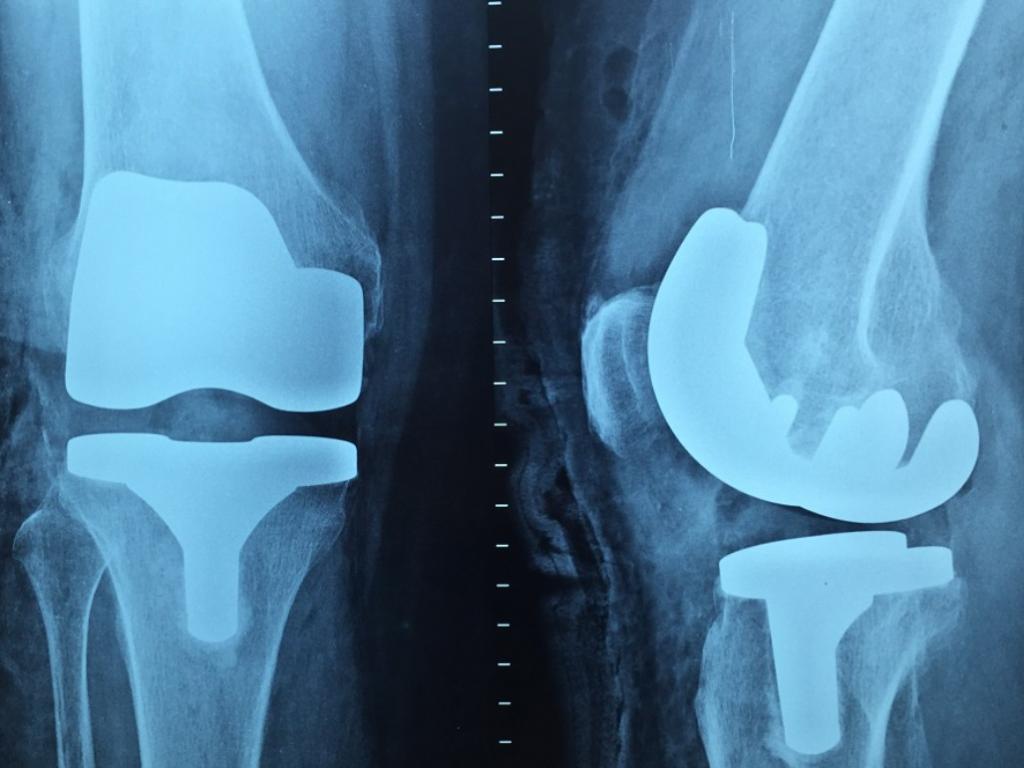

A criança com Síndrome de West e paralisia cerebral grave, se submeteu a uma cirurgia bem-sucedida e foram iniciados os trabalhos de um fisioterapeuta. Porém, após 15 dias de tratamento, a menina passou a sentir dores intensas na perna operada decorrentes de uma segunda fratura, confirmada por exame de imagem.